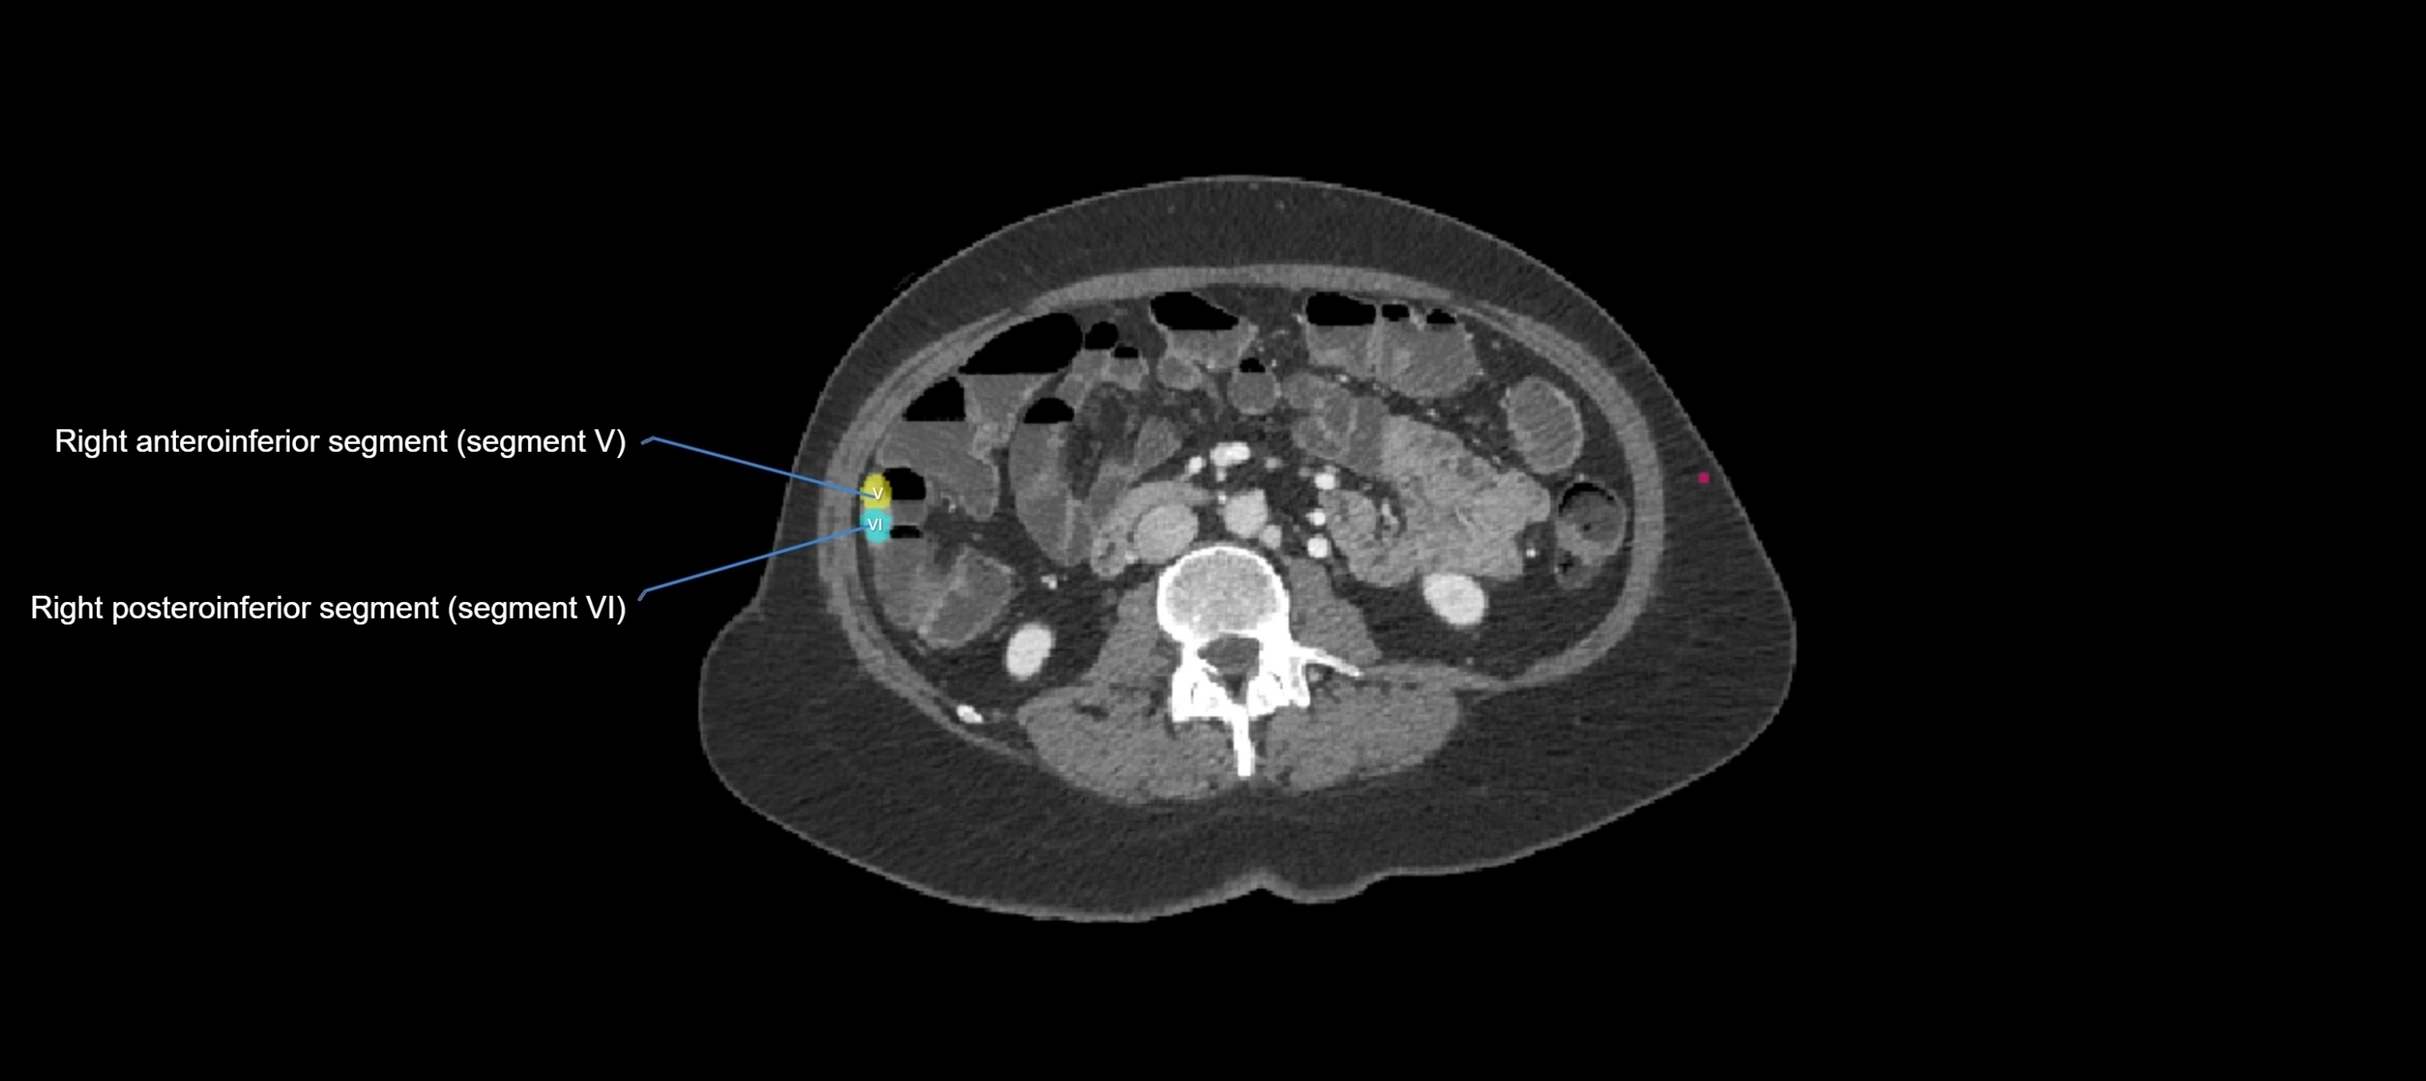

CT Image

image